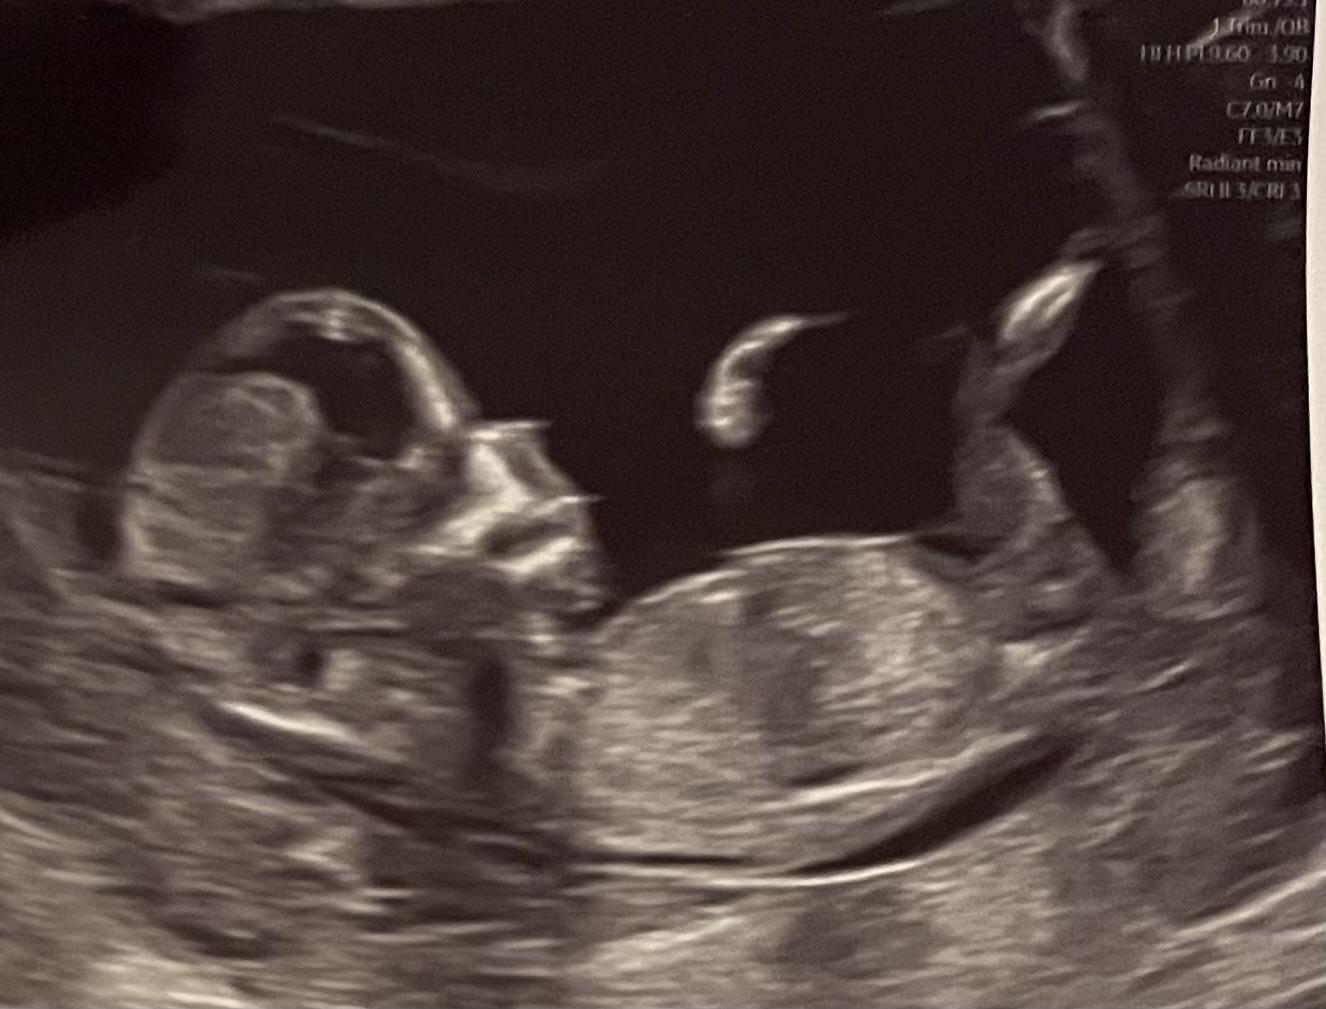

Vidíte na fotce pohlavní hrbolek?

@misha31 jojo, říkala chlapečka, ale mne to, podle čeho to určovala, nepřišlo jako hrbolek, nevidela jsem u nikoho, že by byl ten pahorek tak velký 😀 ale nechtěla jsem se s ni hádat, přece jen, ona by to měla vědět lip než ja, na co kouka 😆 ale tak jsem rada, ze nejsem jediná, komu to prijde spis jako pupečník 😅 tak uvidime no, snad mi na dalším screeningu neřekne neco jiného, počítáme s klukem 😆

@misha31 haha, to by byl fakt gol, kdyby se ta doktorka spletla a čučela na pupečník 😂 ona totiž ukazovala na to, co jsem považovala za pupečník a říkala “pokud je to pohlavní pahorek, tak podle jeho sklonu si myslim, ze to bude na 95% chlapec”, takze to byl docela sebejistý odhad 🤭